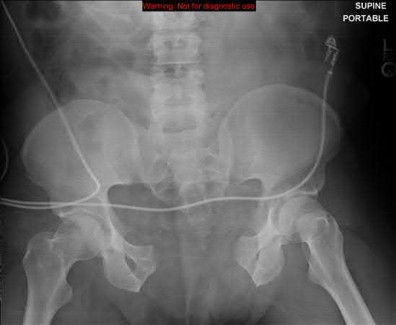

A 35 year-old female presents after prolonged extrication from a motor vehicle collision complaining of severe pelvic pain. Physical examination reveals diminished perianal sensation. She is otherwise neurologically intact. Figures A through D are radiographs and representative CT cuts of her injury. Which of the following nerve roots has likely been injured by the acute trauma?

The clinical scenario is consistent with a high-energy sacral fracture. The radiographs in figures A and B demonstrate a sacral fracture with posterior displacement of the right hemipelvis seen on the inlet view. Figures C and D are axial and sagittal CT images which show a displaced fracture of the right

hemisacrum along with a transvere fracture component through the S3 body . Diminished perianal sensation is concerning for an S2 nerve root injury.

Mehta et al reviewed the current management of sacral fractures. They note that the S1 and S2 nerve roots are more likely to be injured with sacral fractures as they occupy 1/3 to 1/4 of the neural foramina, as opposed to S3 and S4, which only occupy 1/6 of the neural foramina.

Robles reviewed the current literature to ascertain principles of evaluation and treatment for transverse sacral fractures. The author notes that injury to nerve roots S2 to S5 is manifested by impairment of urinary and anal continence and sexual function.